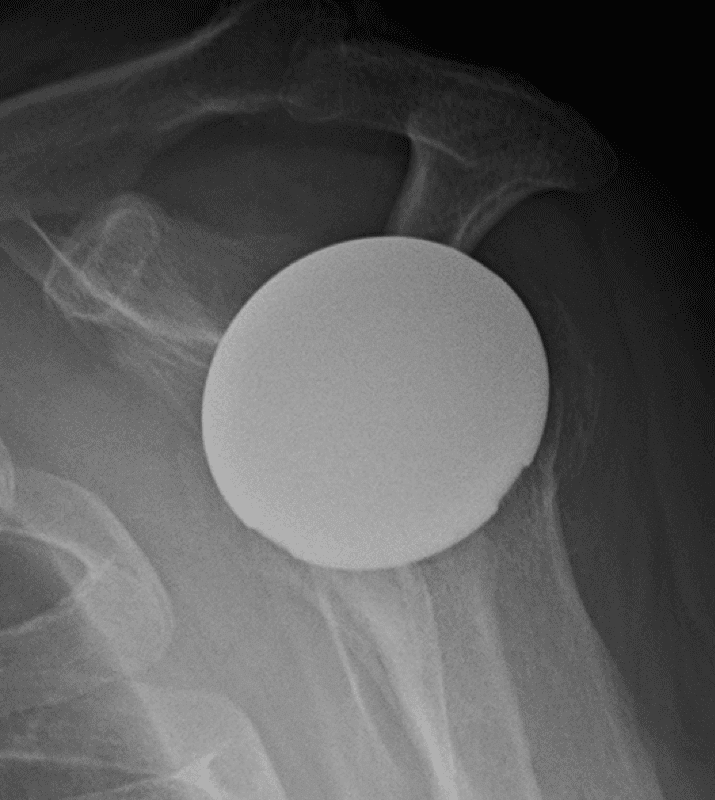

Arthrex, Eclipse